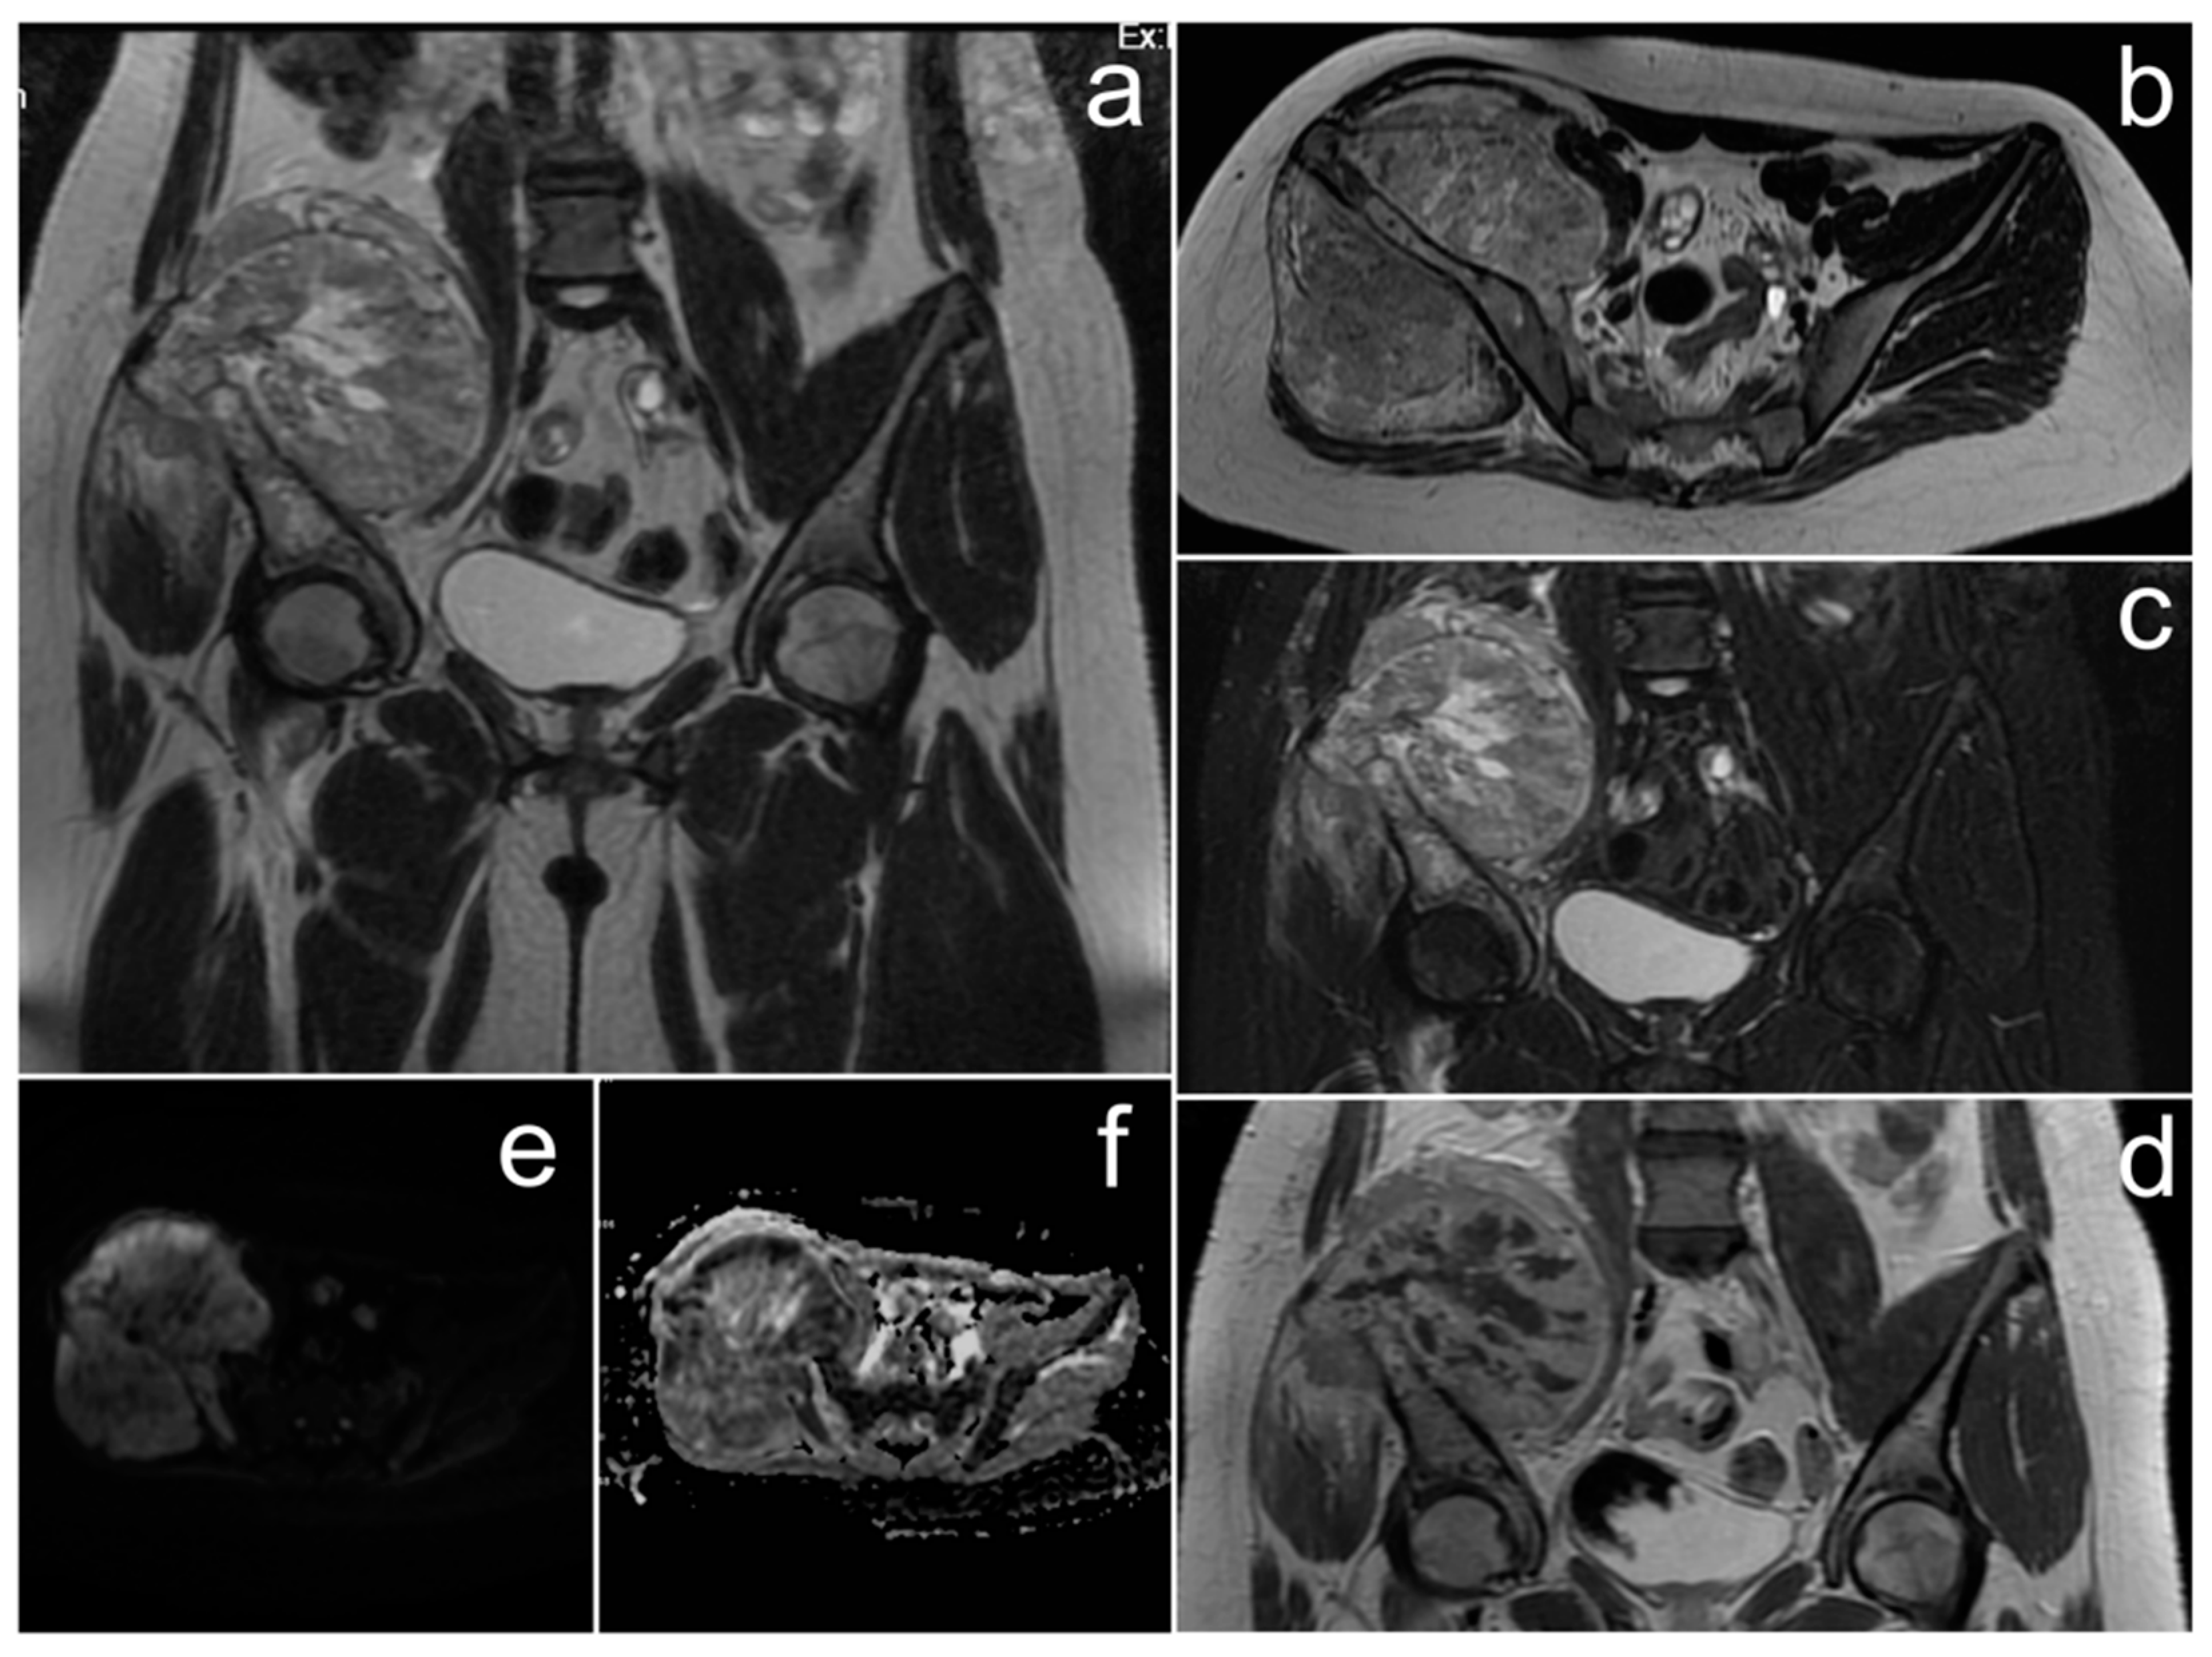

3.4. Ovarian Sertoli–Leydig Cell Tumor with Rhabdomyosarcoma Due to DICER1 Syndrome

Case Report

| Ovarian Sertoli–Leydig cell tumor with rhabdomyosarcoma | variable; solid, solid-cystic, or exclusively cystic; T2 signal depends on amount of fibrous stroma; strong enhancement of solid elements in arterial phase | elevated testosterone level | virilization; associated with DICER1 syndrome |